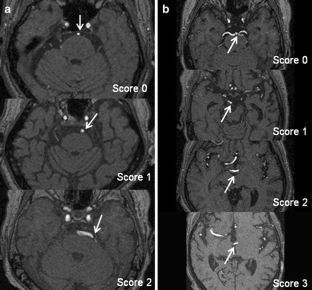

Figure 1